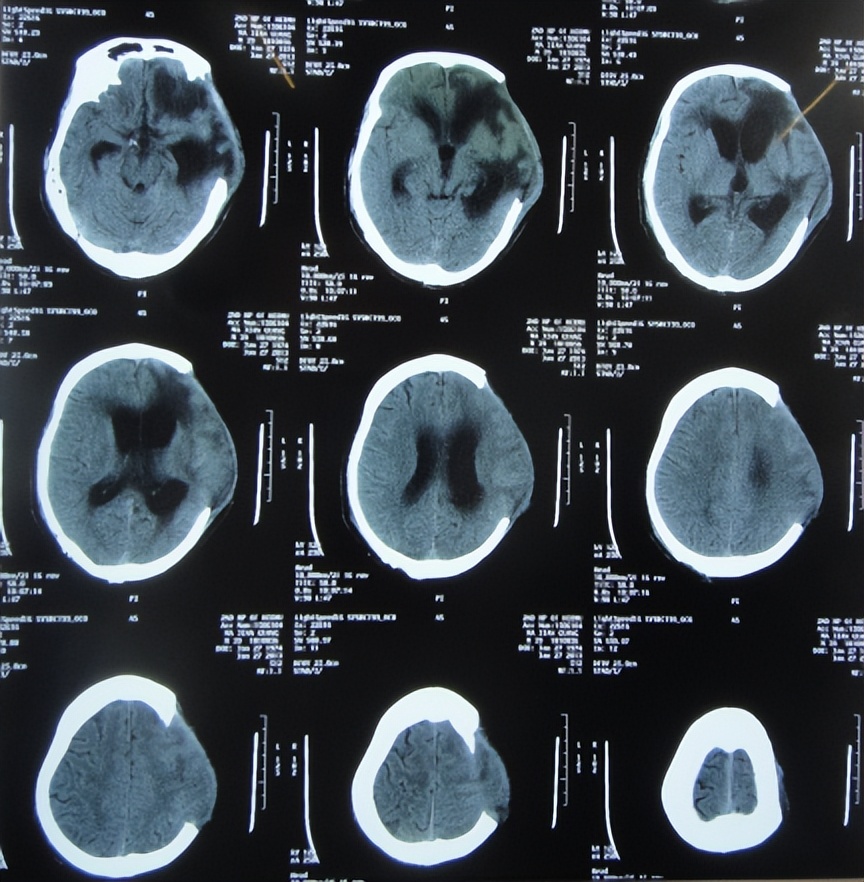

脑脊液各项指标化验正常后于2013年3月26日(治疗21天),进行了左侧脑室-腹腔分流术( 图-14 )。

图-14: 2013年3月26日头颅CT

2013年4月7日(治疗33天)出院,出院时:脑积水颅内感染已治好,意识由入院时昏迷变意识模糊,自动睁眼,遵嘱活动差;左额颞顶区原去骨瓣手术切口破溃已经愈合,大小便变正常( 图-15 );头颅CT示仍遗留颅骨缺损( 图-16 )。

图-16: 2013年4月7日出院时头颅CT

出院后6个月,病情进一步好转为:意识变清楚,肢体能自主活动,还进行了颅骨修补手术。

出院后近4年即2017年2月28日,来院复查。复查时:肢体活动和智力、言语表达均已是健康的正常状态,已投入正常的工作,头颅CT示无异常( 图-17 );特意送来锦旗以表对李小勇脑脊液科的感谢( 图-18 )。

图-17: 2017年2月28日复查